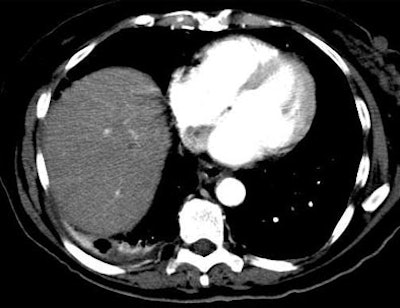

| Another patient with fever after prolonged neutropenia. Above, arterial-phase CT shows a type 2b lesion (arrow). Below, portal-venous phase fails to show a lesion. |

The most marked difference between arterial and portal-venous phase CT could be seen in the detection rate for the hyperdense type 4 lesions, he said. On arterial-phase CT nearly 80% of the lesions had strong enhancement patterns suggestive of infection. Meanwhile, only 40% of the lesions on portal-venous phase CT had such a pattern, and only 45% of the type 4 lesions that could be seen on portal-venous phase CT had such a pattern.

The group performed a phase-based analysis of 536 liver lesions assessed in 36/60 positive studies. Arterial-phase CT identified all 36 (100%) of the positive livers, whereas the portal-venous-phase studies were positive in only 23/36 (69%) of the studies (p<0.001).

"On the lesion-based analysis, arterial-phase (CT) identified 90% (483) of 536 lesions assessed," Metser said, whereas portal-venous-phase CT identified 69% (329/536, p<0.001), and noncontrast CT 57% (265/465, p<0.001), he said. Focal liver lesions were graded as more conspicuous on arterial-phase and non-contrast CT compared to portal-venous phase.